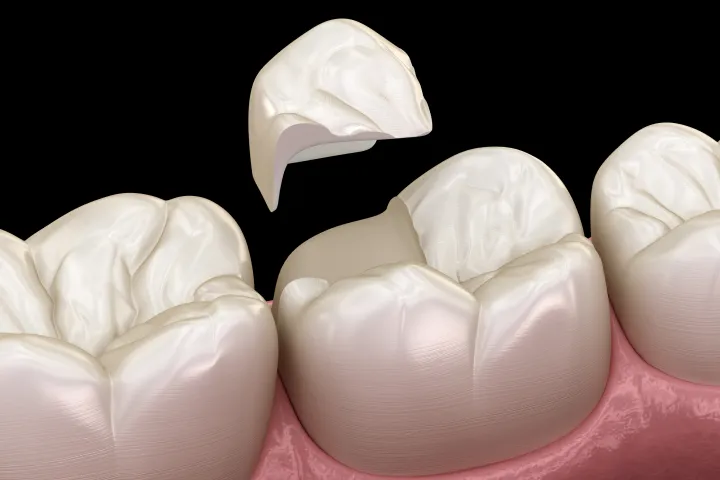

治療後の「歯の寿命」を

延ばすために

根管治療は「土台」であり、その上の

「被せ物」と「噛み合わせ」まで

見据えた包括的治療

根管治療が成功しても、その後に被せるクラウン(被せ物)の精度が低く隙間があれば、そこから細菌が侵入し、再び感染を引き起こします(コロナルリーケージ)。

また、噛み合わせのバランスが悪く、過度な力がかかると、脆くなった歯根は割れてしまいます。

LOTUS DENTAL CLINIC 東京(ロータスデンタルクリニック東京)では、根の治療だけでなく、その後の精密な補綴治療(セラミック治療)や、歯を守るための咬合調整までを一貫して行います。

「木を見て森を見ず」にならないよう、口腔内全体のバランスを整え、治療した歯が10年、20年と機能し続ける環境を構築します。

土台構築・被せ物(補綴)

細菌の侵入を防ぐ精密な土台(ファイバーコア等)を立て、適合精度の高いセラミッククラウンなどを装着し、噛む機能を回復させます。

STEP04

支台築造・機能回復(Fiber Core Restoration)

~歯根破折を防ぐ、しなやかな土台~

根管治療後は、歯の機能を回復させるために被せ物(クラウン)を装着します。その土台となるコアには、天然歯に近い弾性を持つ「ファイバーコア」を採用。金属製の土台に比べて歯根への負担が少なく、治療後の「歯の割れ(歯根破折)」のリスクを大幅に軽減します。